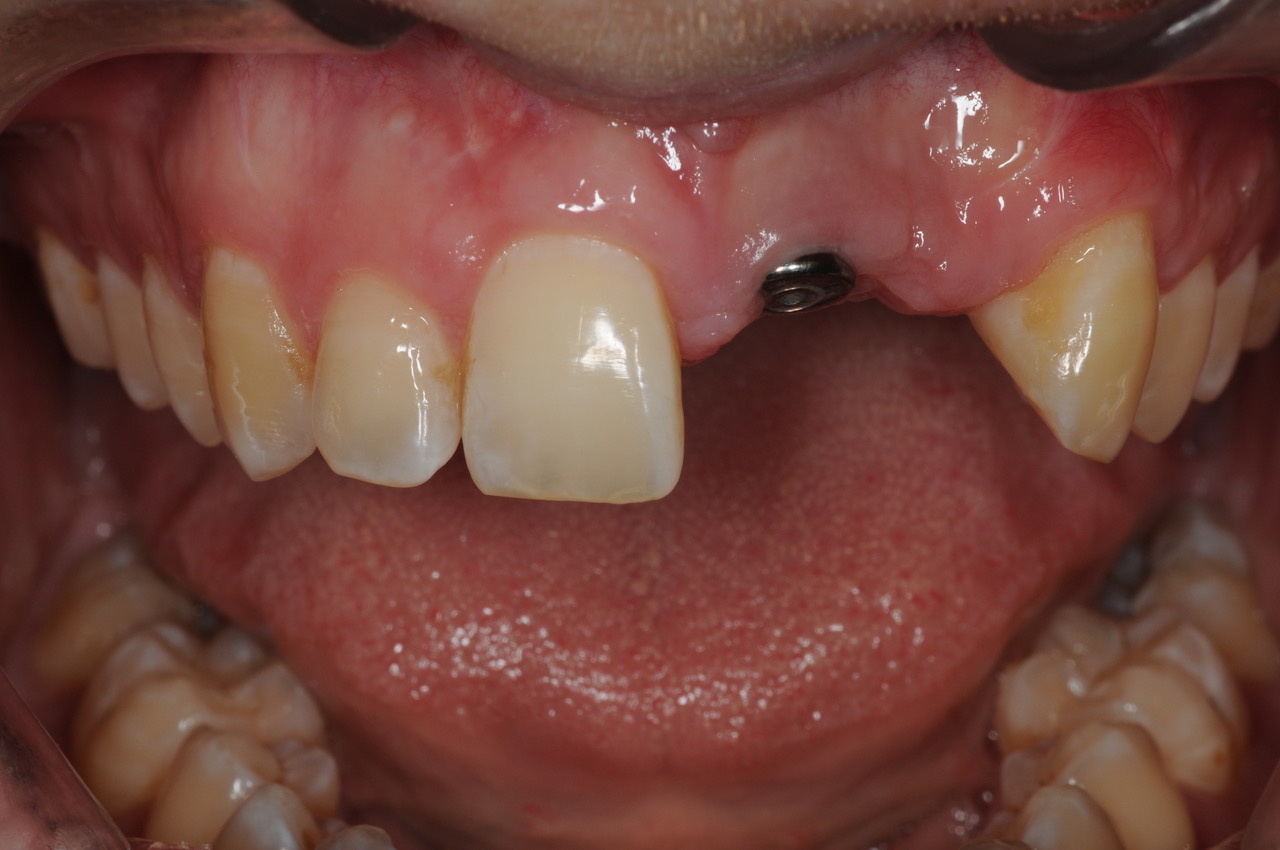

This young man was missing his left central and lateral incisors. He wore a partial denture to replace these two teeth

He did not like the partial denture as it was bulky in his mouth, often came loose while he was eating, and it had stained and worn which made him uncomfortable about his smile.

As the teeth had been missing for many years, there was quite a bone and soft tissue defect. Some grafting procedures were required for this case.

The implant was placed, healing was allowed to progress for nearly 6 months (due to the grafting stages), and the young man continued to wear his partial denture during this time.

One restorative abutment was placed on the implant and then a 2-tooth cantilever bridge was placed on the abutment. The final result appears to be two teeth, but in fact, they are joined together as a bridge, and they are only supported by the one implant, which is in the central incisor position. This design is very functional and also easy for the patient to clean.